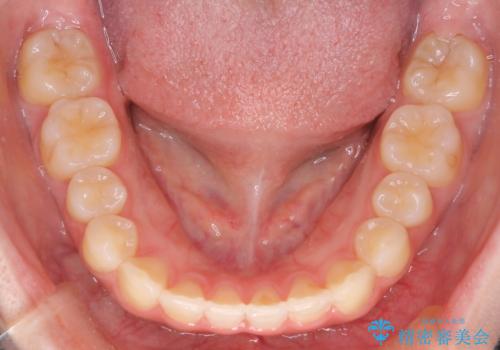

【インビザライン】前歯の凸凹をなおしたい

- 前歯のガタガタを主訴に来院されました。

インビザラインで綺麗な歯並びになり、患者さんには大変満足していただきました。

インビザラインは軽度叢生治療において優れた選択肢となります。